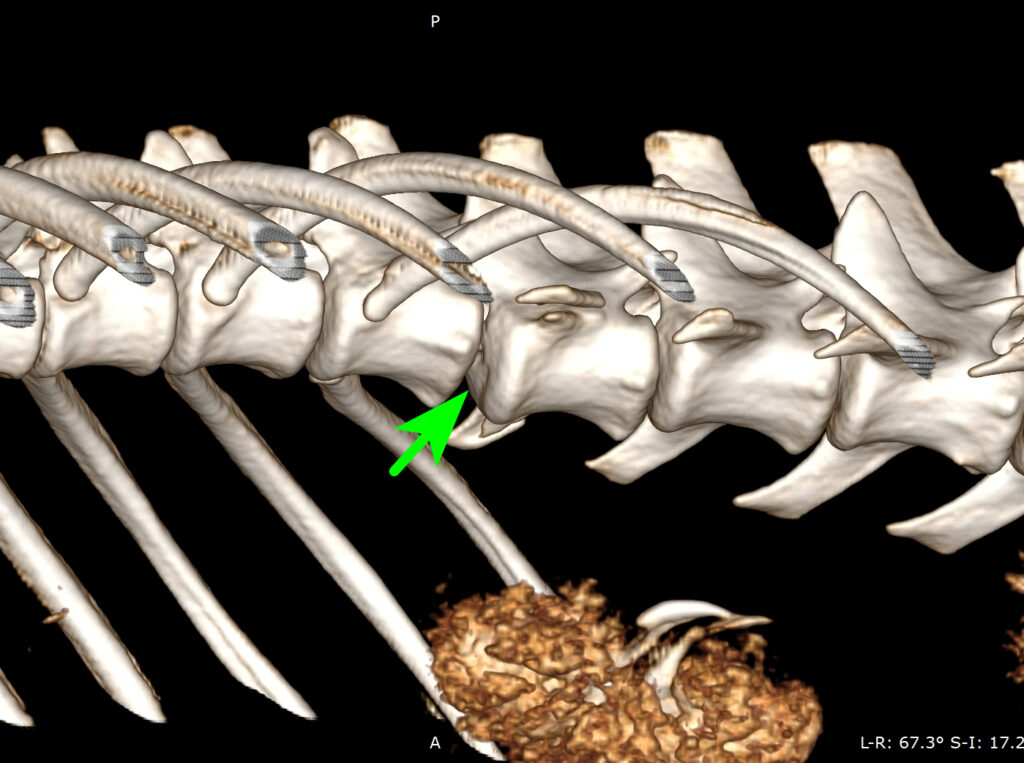

2026-01-01_174525

Stabilisation chirurgicale d’une luxation vertébrale T13–L1 post-traumatique chez un Berger australien.

De gauche à droite et de haut en bas, cette série d’images illustre la prise en charge chirurgicale d’une luxation vertébrale T13–L1 consécutive à un accident de la voie publique. La première image montre la reconstruction tridimensionnelle préopératoire, la flèche verte identifiant précisément le site de la luxation vertébrale. La seconde image correspond au début de l’intervention chirurgicale, avec exposition du foyer lésionnel et réduction progressive de la luxation à l’aide de daviers, sous contrôle visuel strict. La troisième image illustre l’implantation des broches de stabilisation vertébrale, un temps particulièrement délicat nécessitant un positionnement millimétrique selon des angles prédéfinis à partir de l’analyse scanner préopératoire. La quatrième image montre l’ensemble des broches une fois mises en place dans le rachis, assurant la stabilisation segmentaire. La cinquième image correspond à la phase de consolidation du montage, après recoupe des broches et mise en place d’un ciment de polyméthylméthacrylate permettant de solidariser l’ensemble. Enfin, la dernière image présente le contrôle scanner post-opératoire immédiat, confirmant le positionnement correct des implants, l’absence de pénétration dans le canal médullaire et la restauration satisfaisante de l’alignement vertébral.